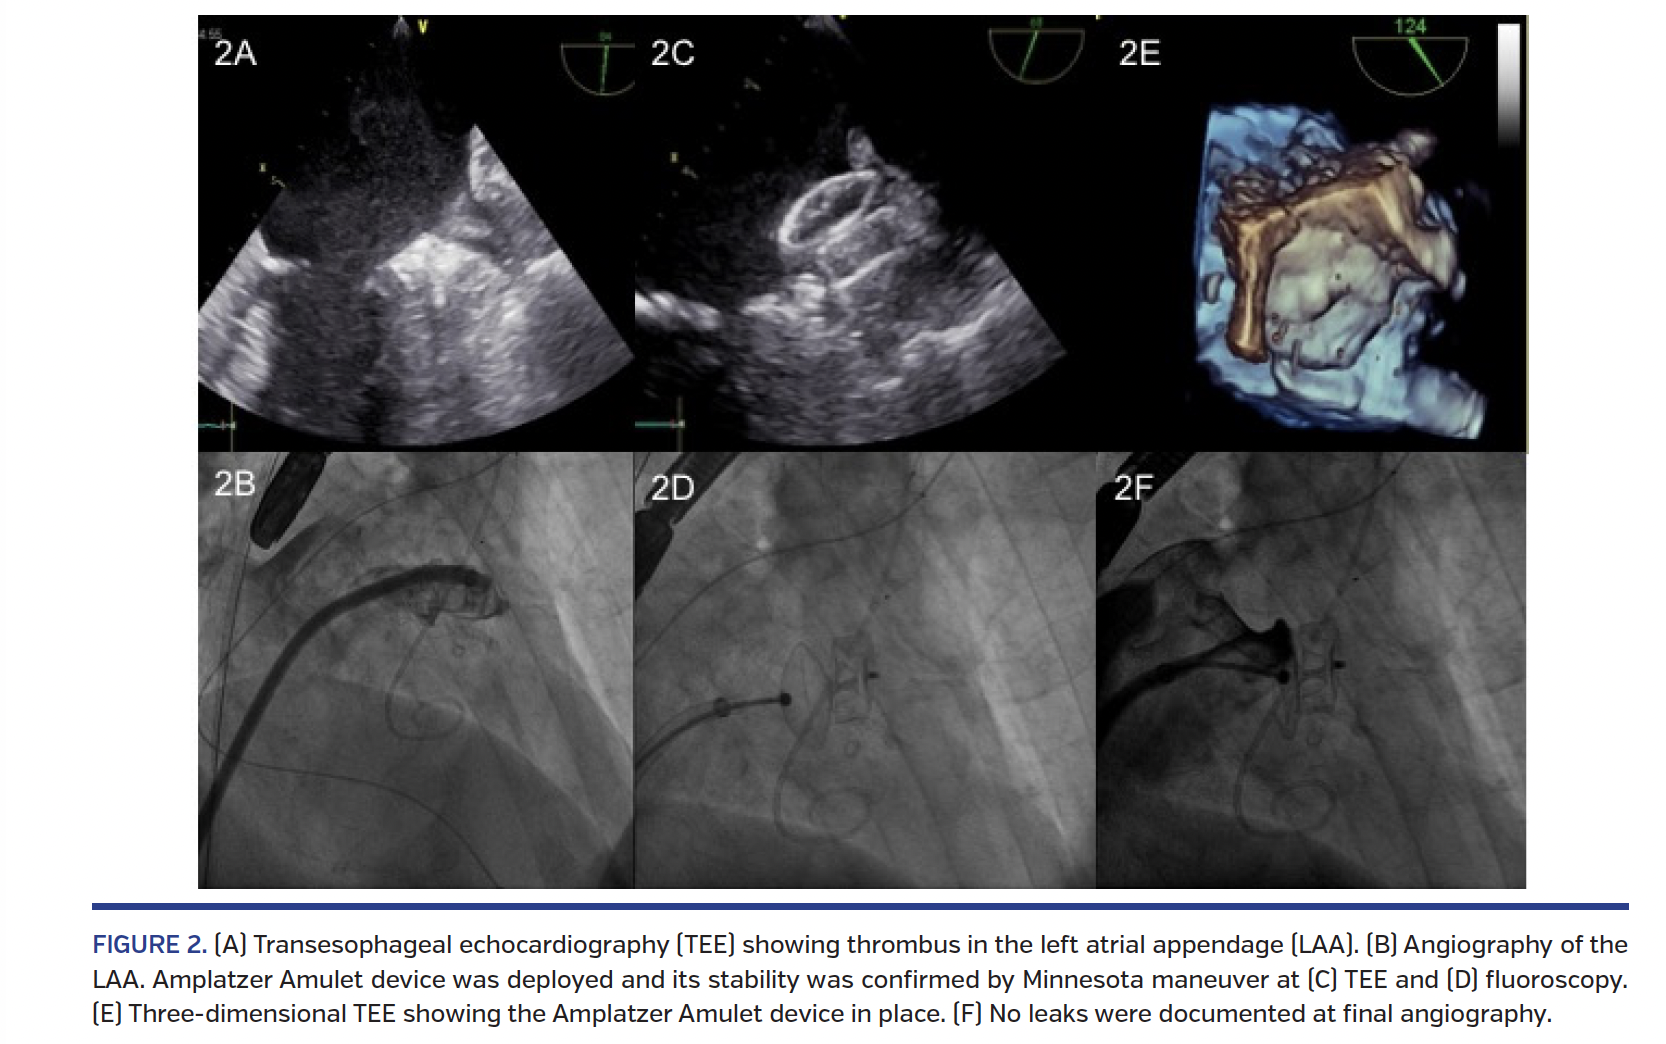

An 83-year-old man was referred for left atrial appendage (LAA) closure at our institution. History included permanent atrial fibrillation (AF) with high thrombotic risk (CHA2DS2-VASc score 6) and bleeding risk (HAS-BLED score 6), recent left main and left circumflex drug-eluting stent implantation, and prior history of brachial artery embolism. The patient needed prolonged dual-antiplatelet therapy due to recent coronary stenting and anticoagulation because of AF at high thrombotic risk. Therefore, we decided to perform percutaneous LAA closure in order to avoid the high bleeding risk related to triple antithrombotic therapy (TAPT). Transesophageal echocardiography (TEE) performed before the procedure revealed a thrombus in the LAA. As a result, he was discharged on TAPT with an increase in target international normalized ratio (range, 2.5-3). TEE performed after 4 and 8 weeks of treatment showed only a mild reduction in thrombus size. Since the patient had a prior history of embolism, an elevated bleeding risk, and documentation of persistent LAA thrombus despite anticoagulation, we decided to proceed with percutaneous LAA closure with concomitant use of a cerebral protection device. The TriGuard embolic protection device (EPD; Keystone Heart Ltd) was chosen for this purpose. It is a nitinol-frame mesh filter that is placed into the aortic arch and covers all three aortic arch arteries, maintaining blood flow to the cerebral vessels through 250 µm pores while deflecting larger emboli to the descending aorta. First, right femoral vein and left femoral artery (FA) accesses were obtained. Unfractionated heparin was given in order to obtain an activated clotting time of ~250 s. An angiogram of the aortic arch was performed (Figure 1A) and the TriGuard EPD, folded into a 7 Fr Mullins sheath, was delivered from the left FA into the ascending aorta. Placement was achieved via uncovering the device by pulling back the sheath (Figures 1B, 1C) and allowing the deflector to open up in the aortic arch (Figure 1D). A pigtail catheter was inserted to facilitate close contact of the device against the ostia of the cerebral vessels. The standard procedure of percutaneous LAA closure was followed, and a 22 mm Amplatzer Amulet was successfully deployed (Figure 2) followed by TriGuard EPD removal. The patient’s postoperative course was uneventful.

We report on first-in-man percutaneous LAA closure with the Amplatzer Amulet device in the presence of LAA thrombus using the TriGuard EPD as a cerebral protection device.